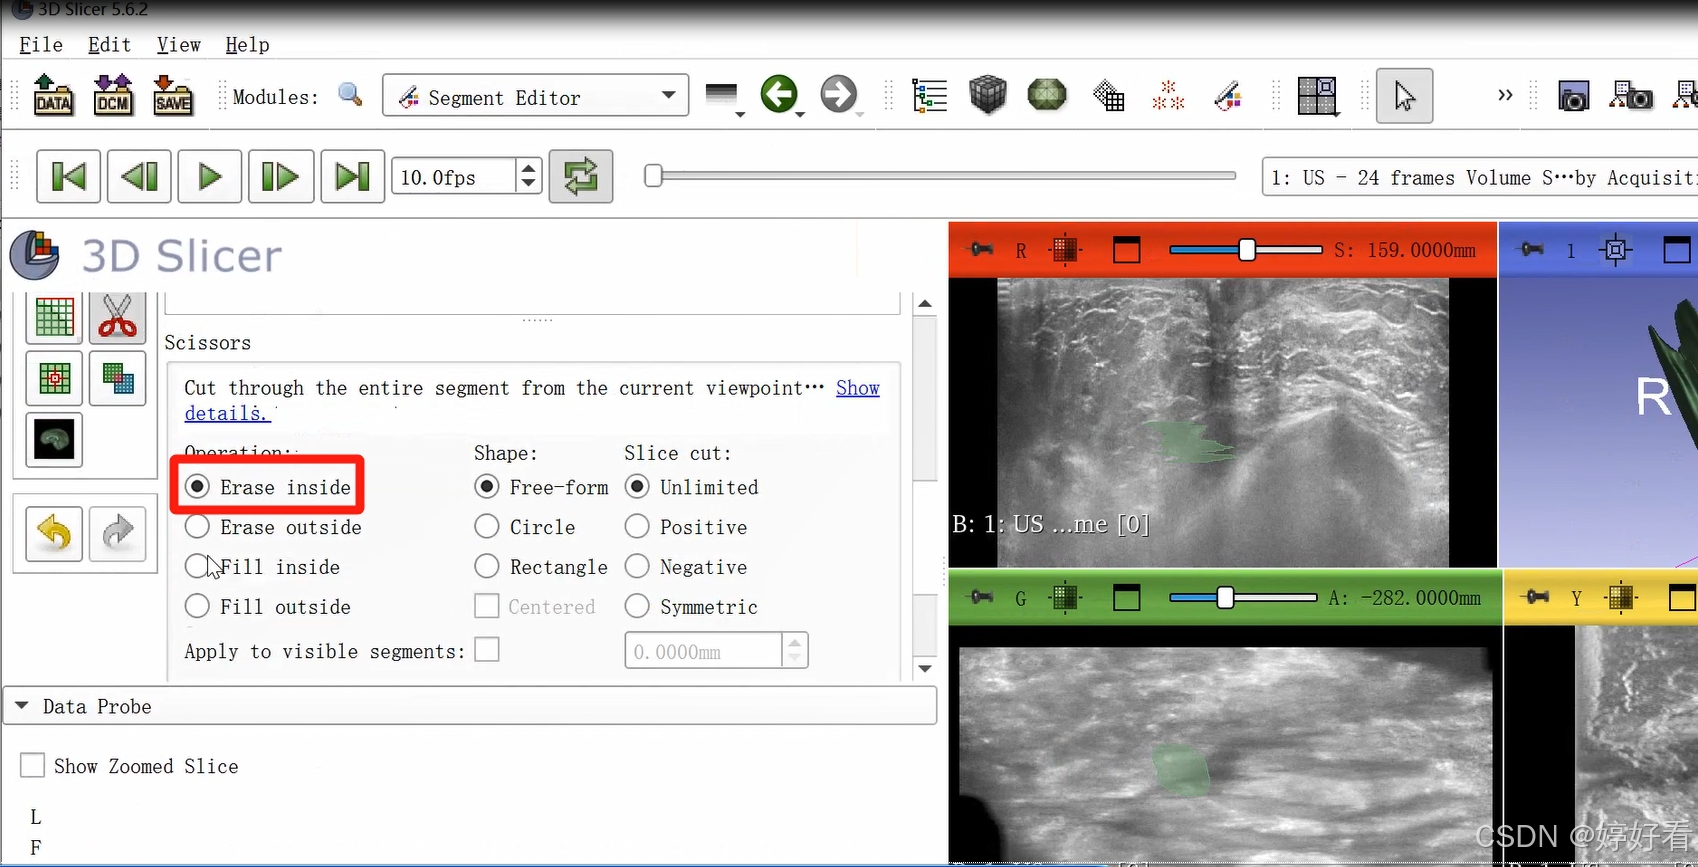

2.8 剪刀功能

剪刀功能的选项较多。以第一个Erase inside功能为例,也就是把圈起来部分里面的内容减掉。